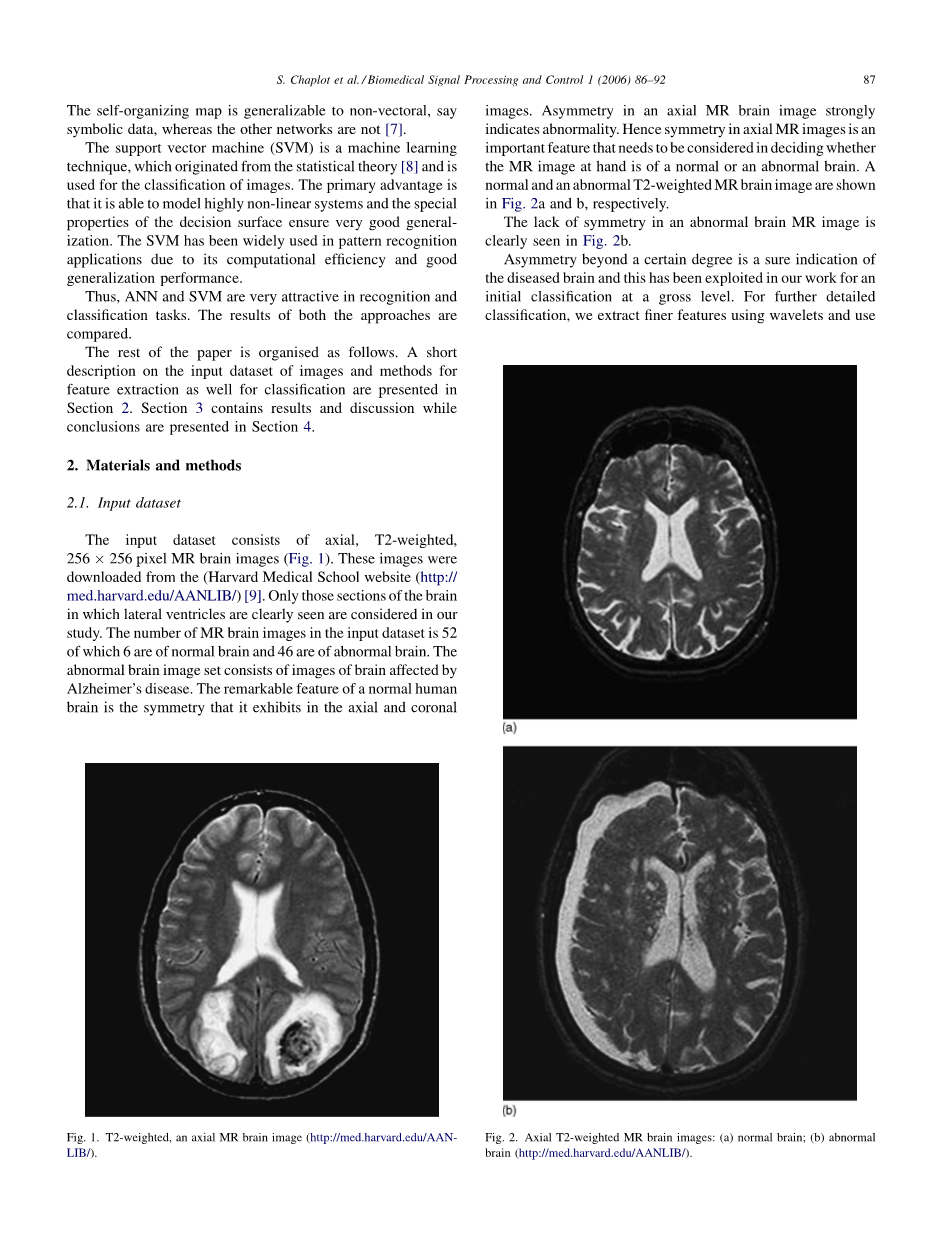

输入数据集由轴向,T2加权,256times;256像素MR脑

图像组成(图1)。这些图像是从(哈佛医学院网站(http:// med.harvard.edu/AANLIB/)[9]下载。在我们的研究中,只考虑了能够清楚地看到侧脑室的大脑部分.MR脑部的数量输入数据集中的图像中有52个,其中6个是正常脑,46个是异常脑。异常脑图像集由受阿尔茨海默病影响的大脑图像组成。正常人脑的显着特征是它呈现的对称性在轴向和冠状

图1.T2加权,轴向MR脑图像(http://med.harvard.edu/AAN-LIB/)。

图片。轴向MR脑图像中的不对称性强烈表明异常。因此,轴向MR图像中的对称性是在决定手边的MR图像是正常脑还是异常脑时需要考虑的重要特征。正常和异常的T2加权MR脑图像分别如图2a和b所示。

在图b中清楚地看到异常脑MR图像中缺乏对称性。

超过一定程度的不对称性是患病大脑的确定指示,并且这已经在我们的工作中用于初级分类。为了进一步详细分类,我们使用小波和使用提取更精细的特征

图2.轴向T2加权MR脑图像:(a)正常脑; (b)大脑异常(http://med.harvard.edu/AANLIB/)。